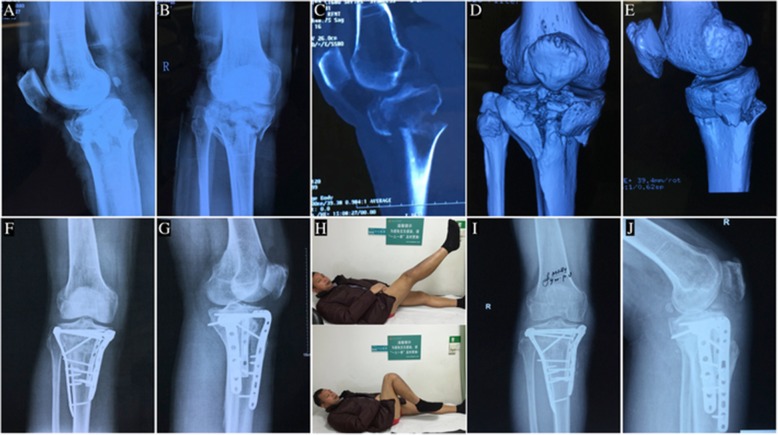

Fig. 3.

A 48-year-old man with hyperextension bicondylar tibial plateau fracture treated with anterolateral and posteromedial double incisions. a Preoperative anteroposterior view of X-ray. b Preoperative lateral view of X-ray shows a reversed pTSA. c,d,e Three-dimensional reconstruction CT shows collapse of the anterior part of tibial plateau and a large displacement of the posterior tibial cortex. f,g Postoperative anteroposterior view and lateral view of X-ray. h The function of the knee has recovered at the 9-month follow up. i,j Anteroposterior view and lateral view of X-ray show the fracture has healed at the 9-month follow up